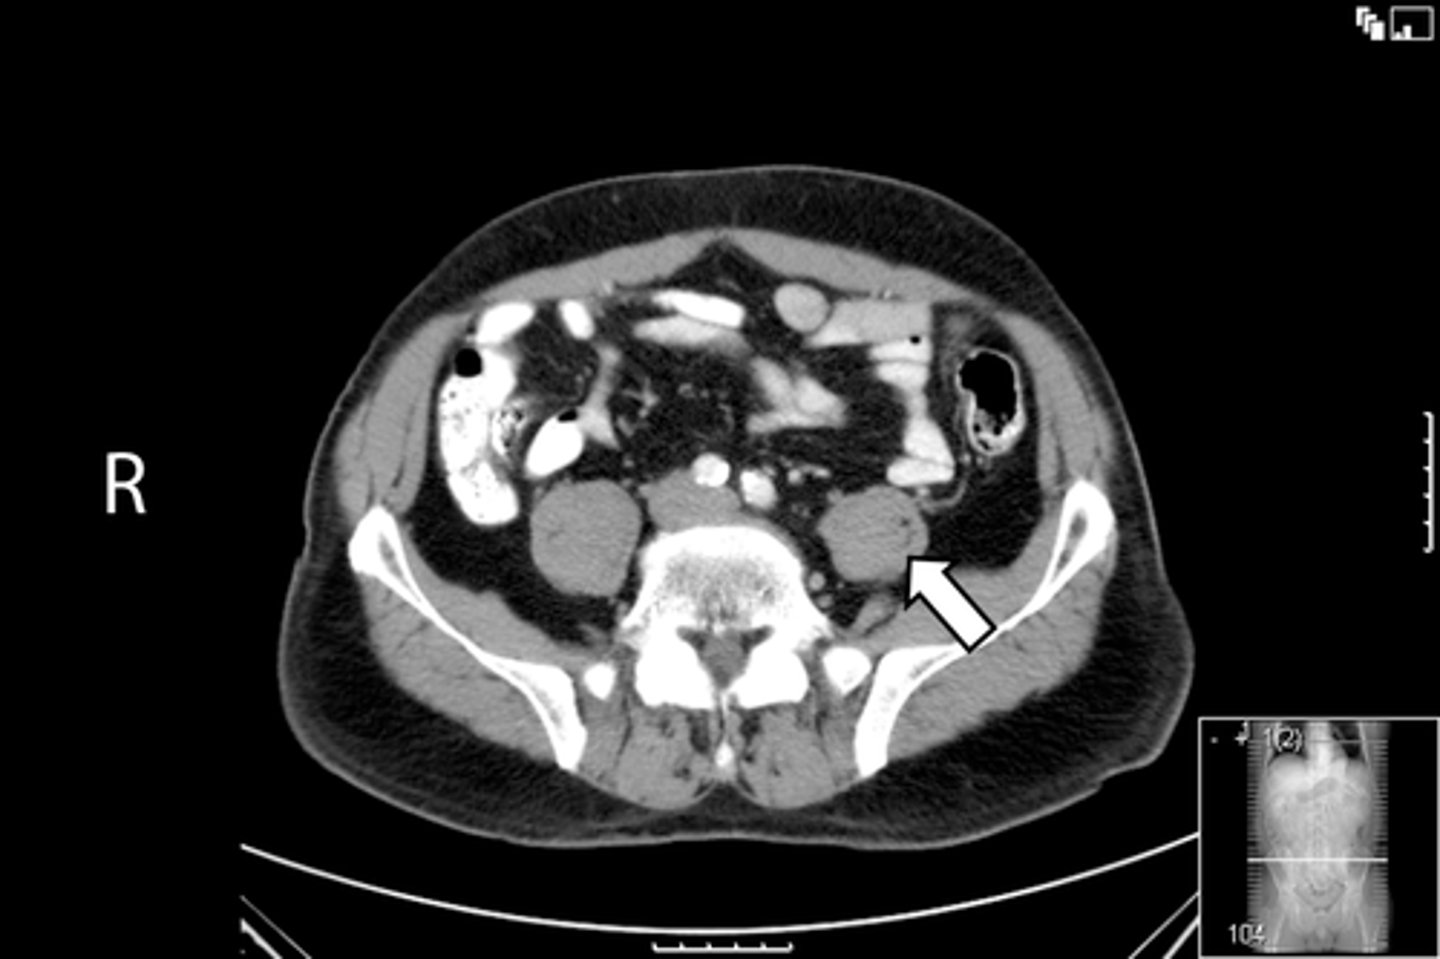

Axial bony pelvis CT

What is the image?

L acetabulum

What is indicated in the image?

L femoral head

L piriformis muscle

R femoral head

R piriformis muscle

R acetabulum (posterior part)

Sacrum